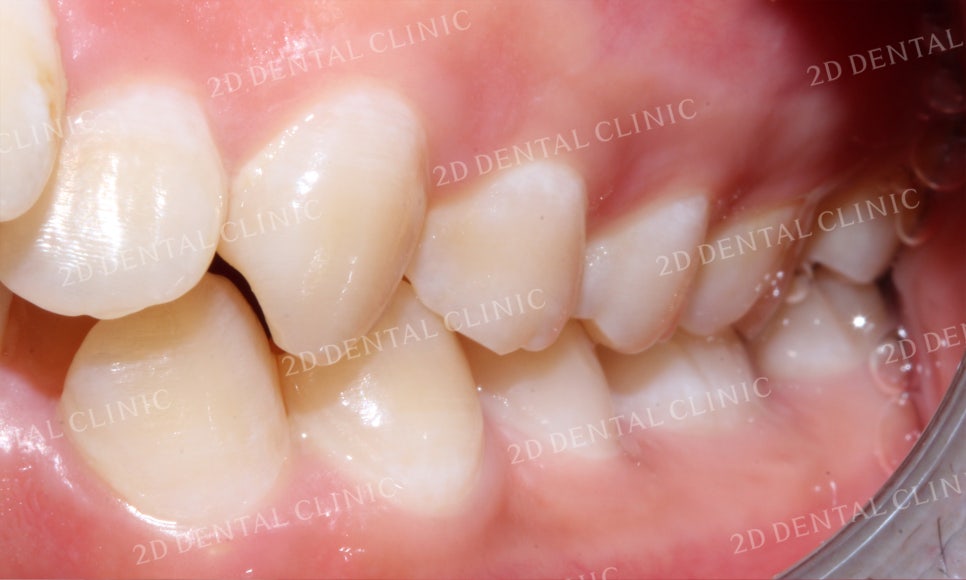

우측 구치부 역시 좌측과 같은 상태로

상하악 교합이 깊게 물리는 모습입니다.